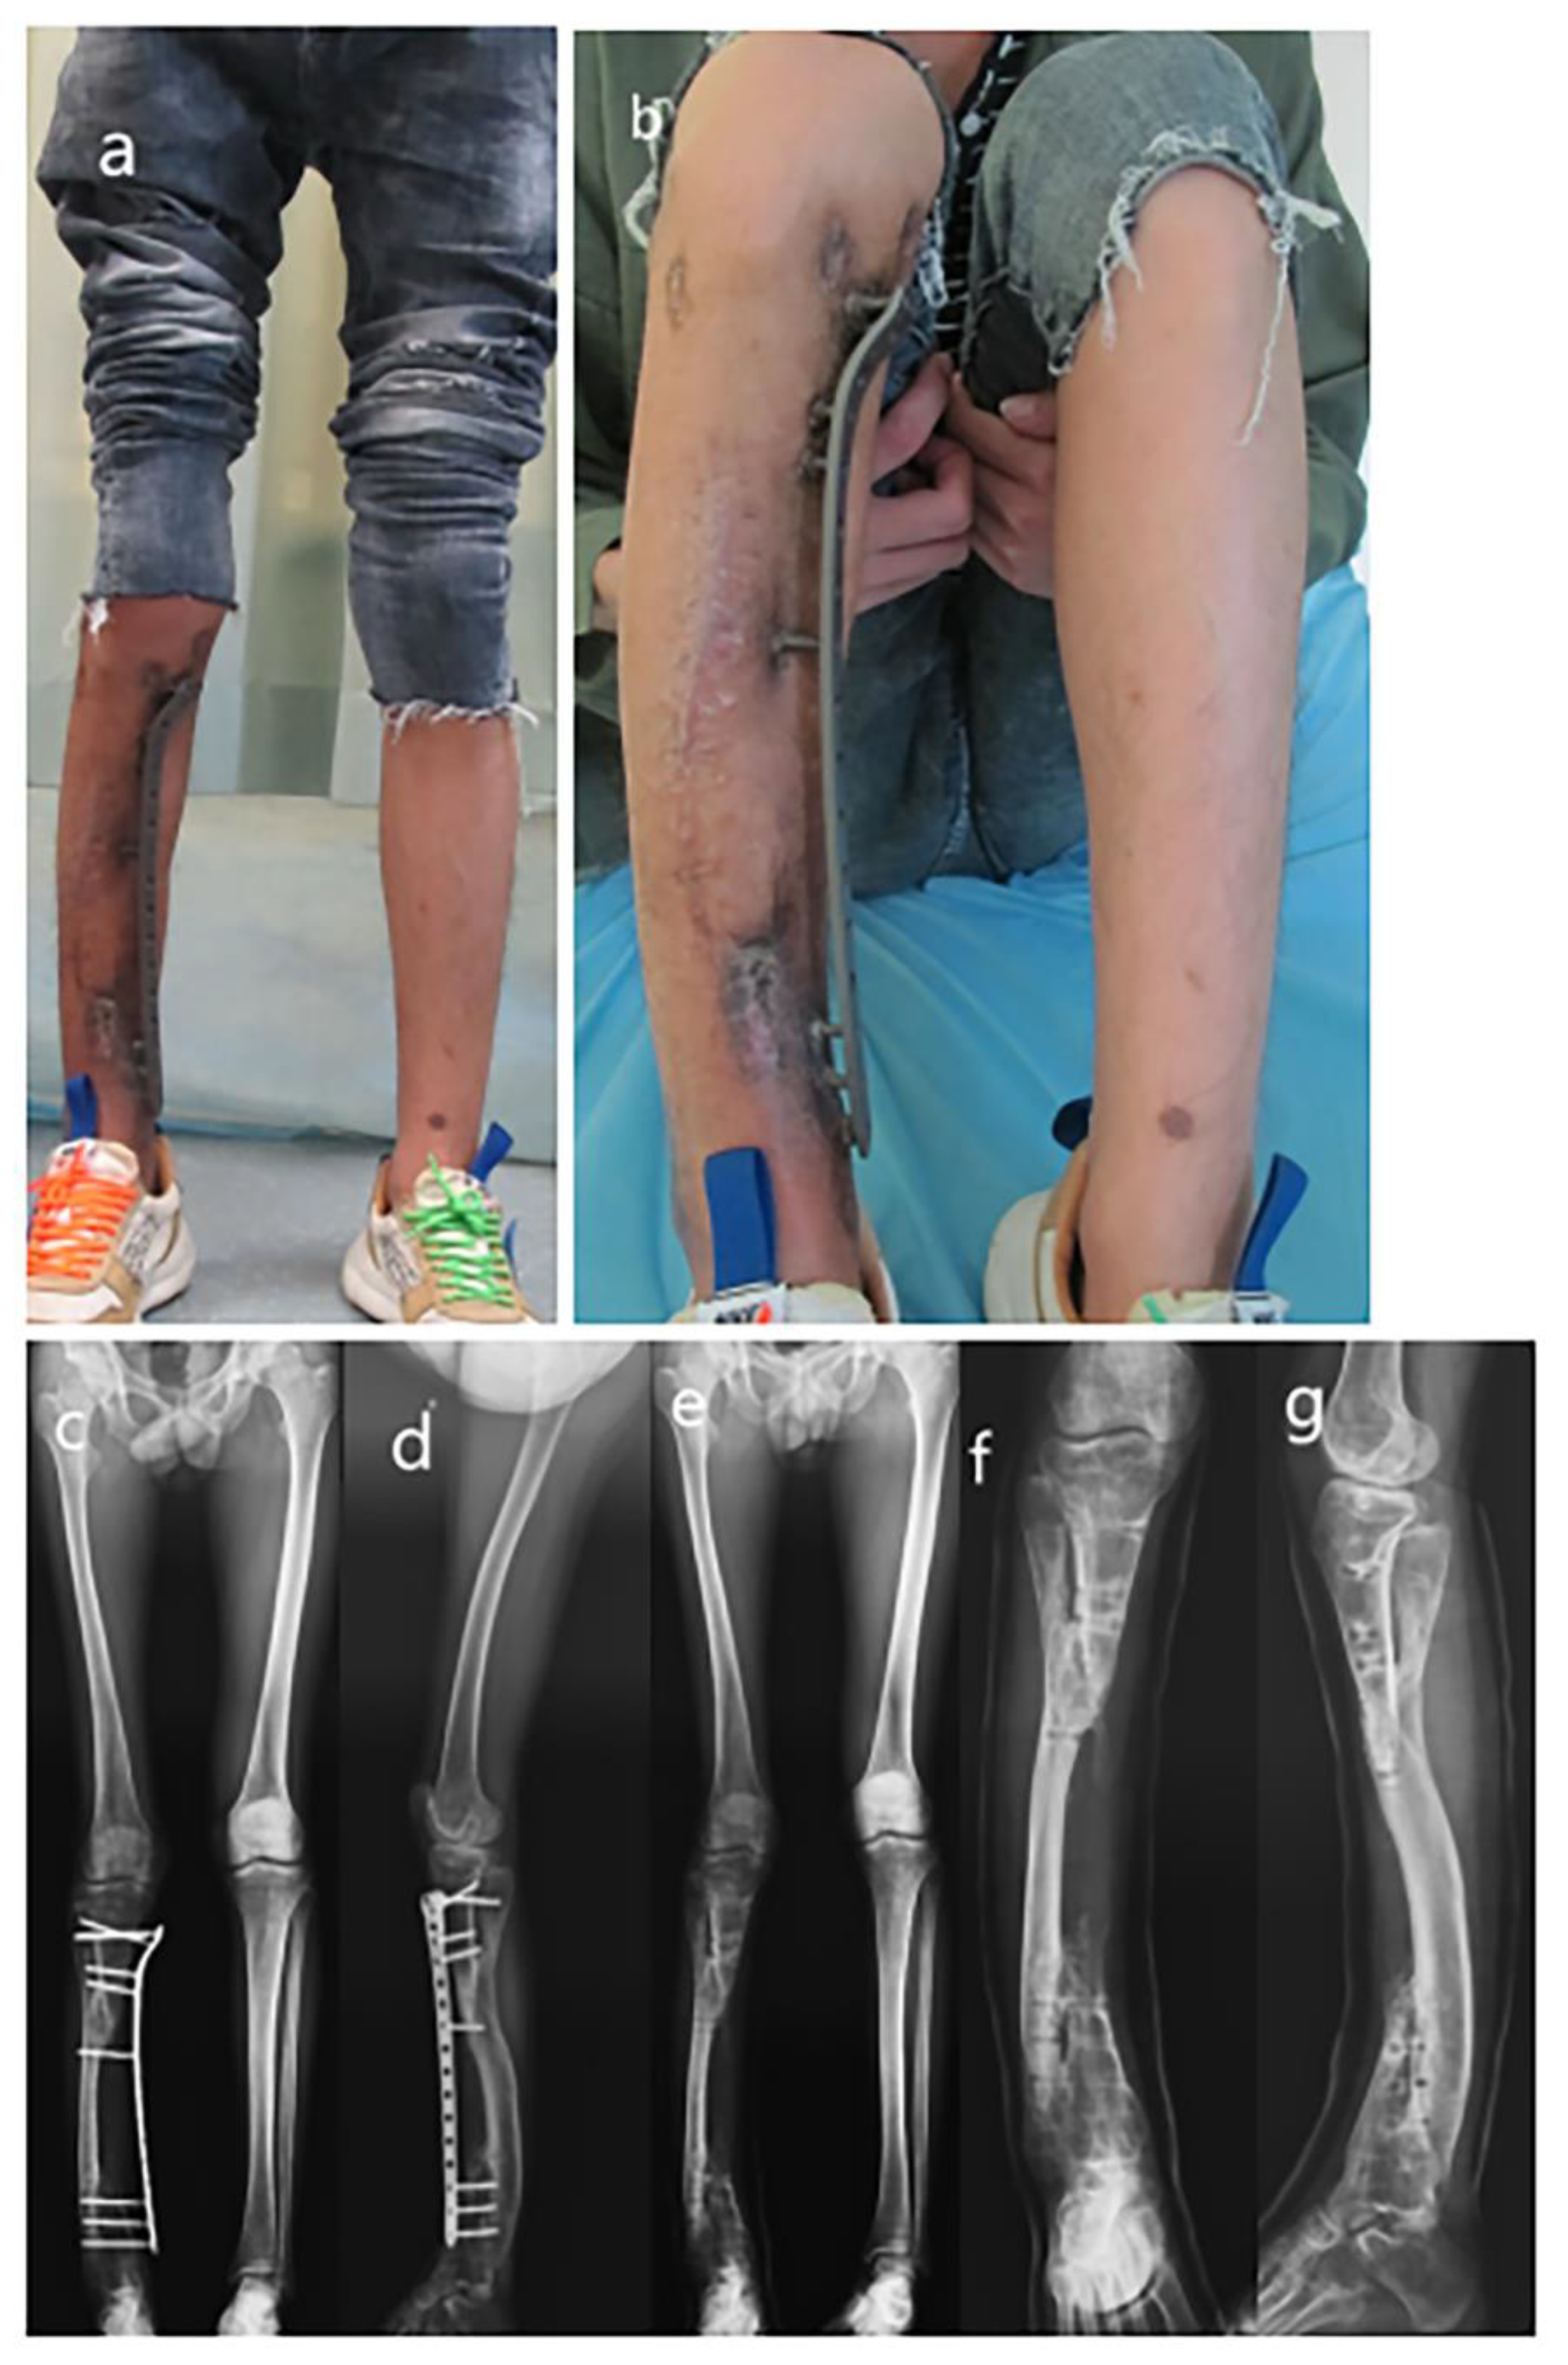

Figure 4.

The appearance of the lower extremity and removal of the plate. (a) The appearance of the lower extremities; (b) Flexion of the knee joint; (c) AP view full-length radiograph of lower extremities before plate removal; (d) Lateral view full-length radiograph of lower extremities before plate removal; (e) AP view full-length radiograph of lower extremities after plate removal; (f) AP view radiograph of tibia–fibula after plate removal; (g) Lateral view radiograph of tibia–fibula after plate removal.